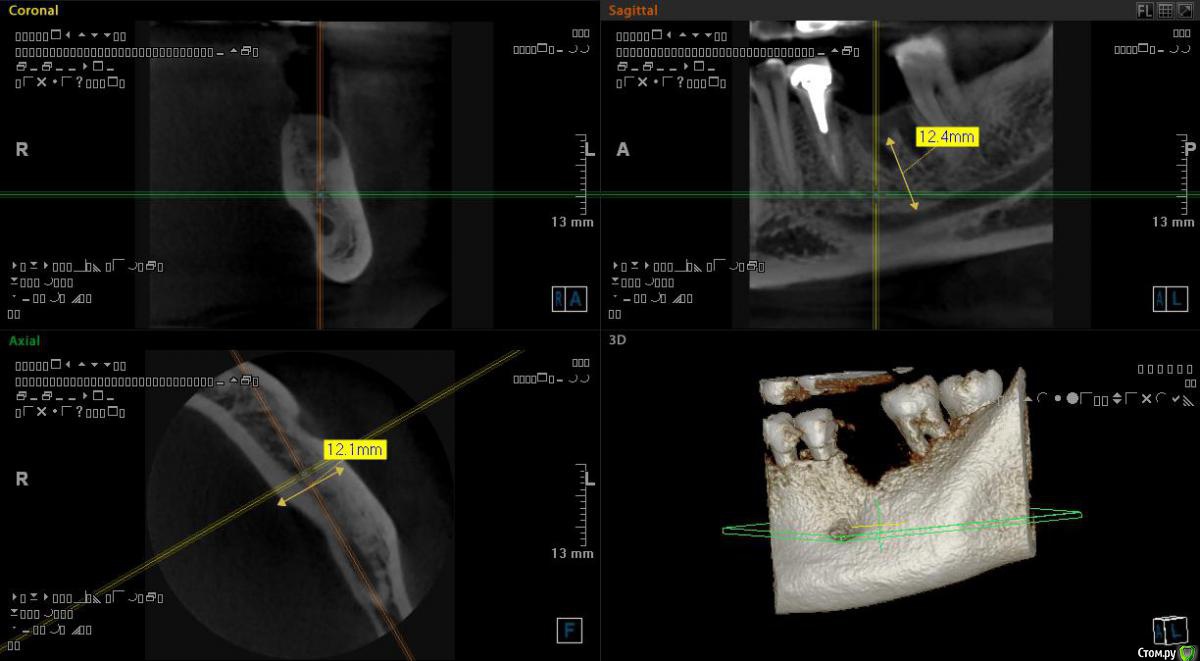

Самарец Опубликовано 11 августа, 2020 Автор Поделиться Опубликовано 11 августа, 2020 срезы выставлены не корректно, покажите еще, в том числе в области седьмого зубаСпасибо за ответ. Так пойдёт? Ссылка на комментарий

Irouil Опубликовано 11 августа, 2020 Поделиться Опубликовано 11 августа, 2020 Все в порядке 1 Ссылка на комментарий